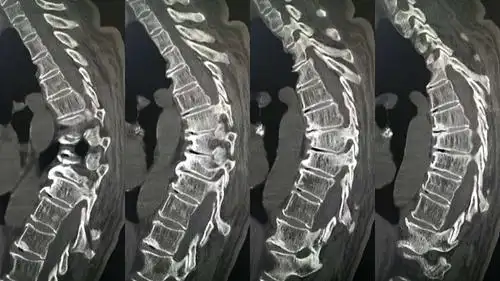

术前胸椎ct失状面三维重建